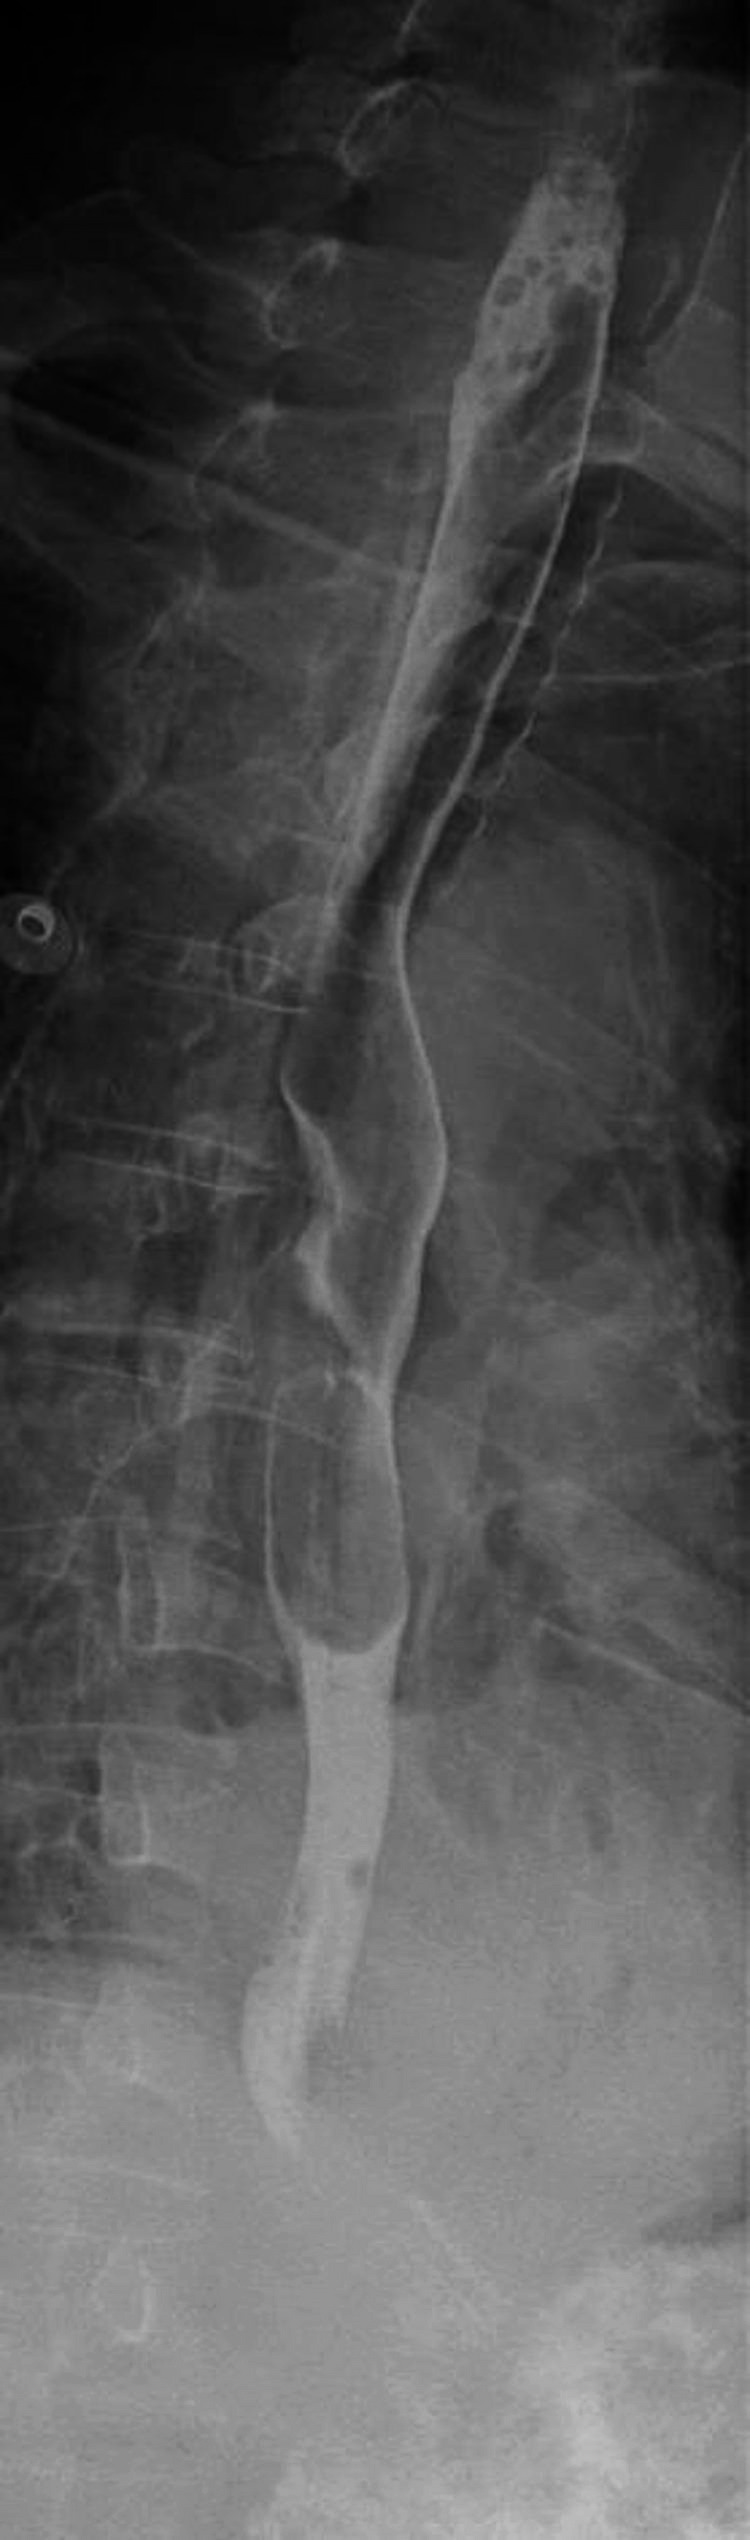

Case presentation: The 65-year-old male patient who was admitted to the emergency department with left chest pain and dyspnoea after severe vomiting. Chest computed tomography (CT) indicated left hydropneumothorax and mediastinal emphysema. The patient underwent bedside closed thoracic drainage. The drainage fluid was coffee-coloured and turbid, with significantly elevated CA199, CA125 and CEA levels. After transferring the patient to the emergency operating room, the esophageal defect was repaired, and a jejunostomy was performed. No tumours were detected in the thoracic cavity during surgery. The patient recovered and was discharged from the hospital.

Conclusion: Esophageal tumours should be suspected in patients with elevated pleural effusion CA199, CA125 and CEA levels. The findings from chest CT and oesophagography did not support the diagnosis of a thoracic tumor.These tumor markers may be concomitant changes during esophageal rupture.